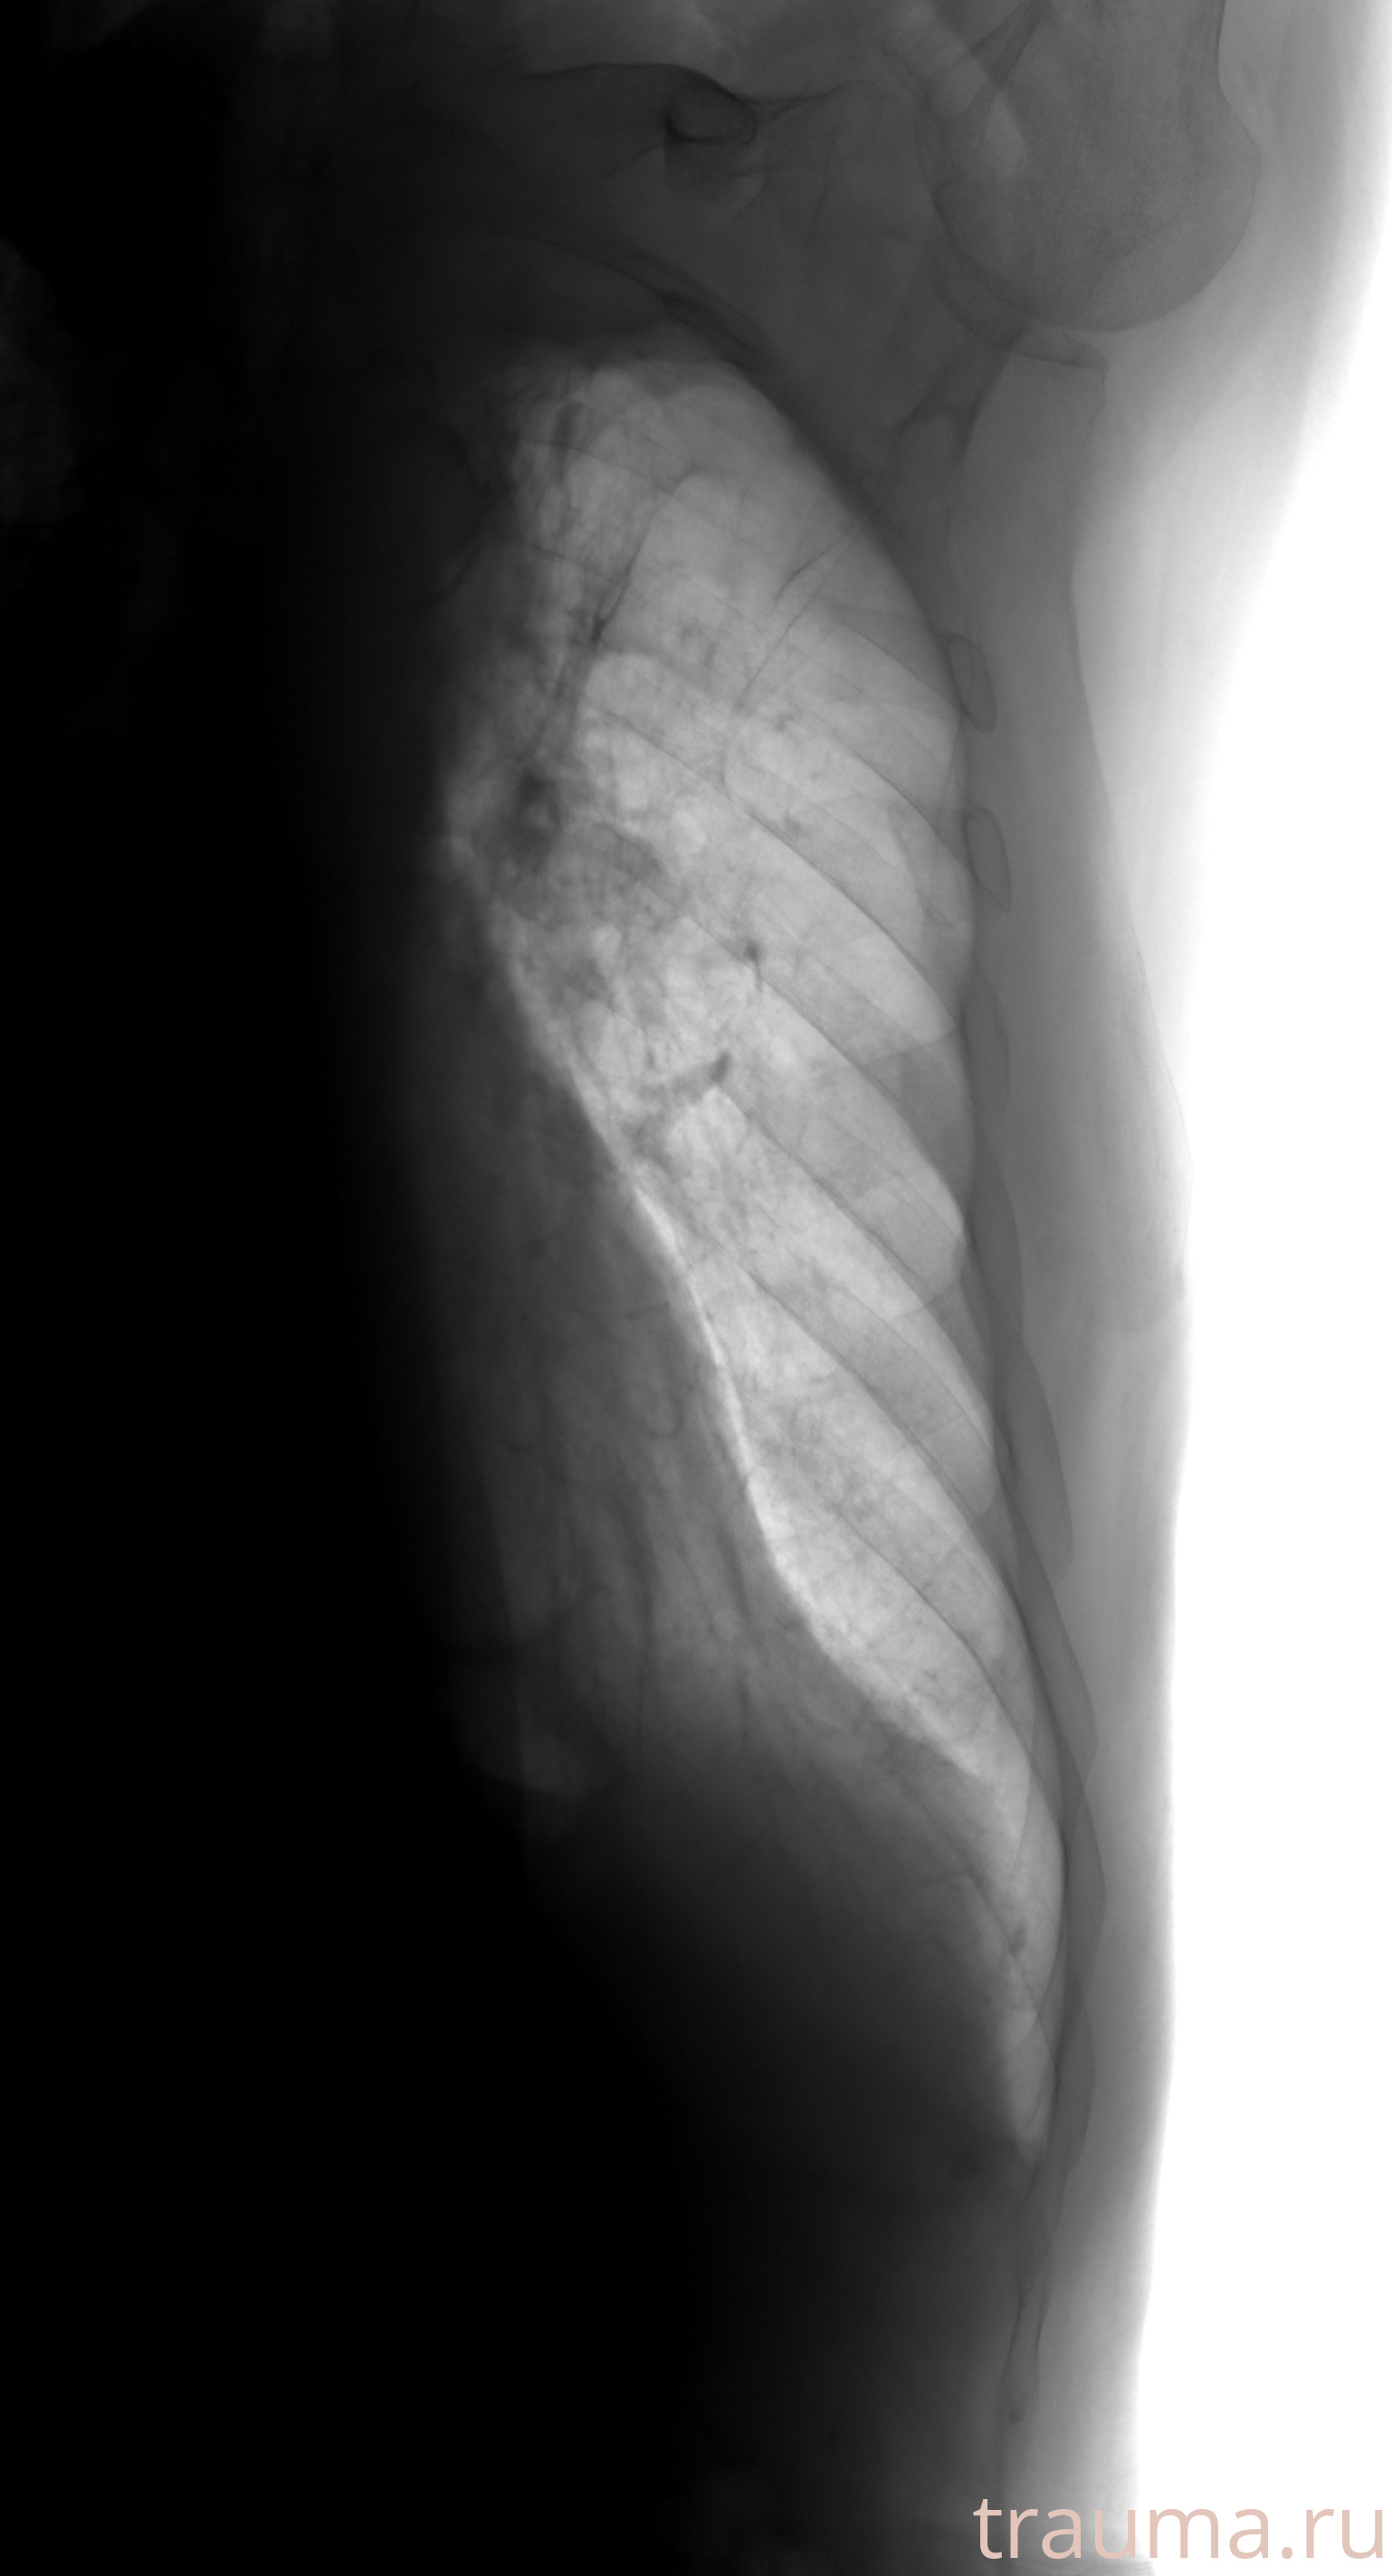

Рентген на дому: по вашему адресу приезжает врач-рентгенолог, травматолог-ортопед с мобильным рентгеновским аппаратом, проводит диагностику травмы или заболевания, делает необходимые рентгенограммы, дает рекомендации по дальнейшему лечению. Получить качественные снимки в домашних условиях возможно благодаря уникальной методике, разработанной МосРентген Центром для института  Склифосовского